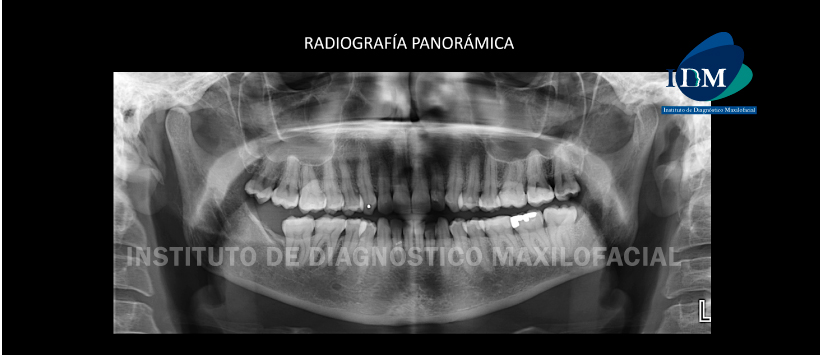

A la evaluación de la radiografía panorámica se evidencia una neumatización alveolar de ambos senos maxilares, leve apiñamiento dentario anterior, múltiples restauraciones y ausencia de la pieza 48. (Figura 1)